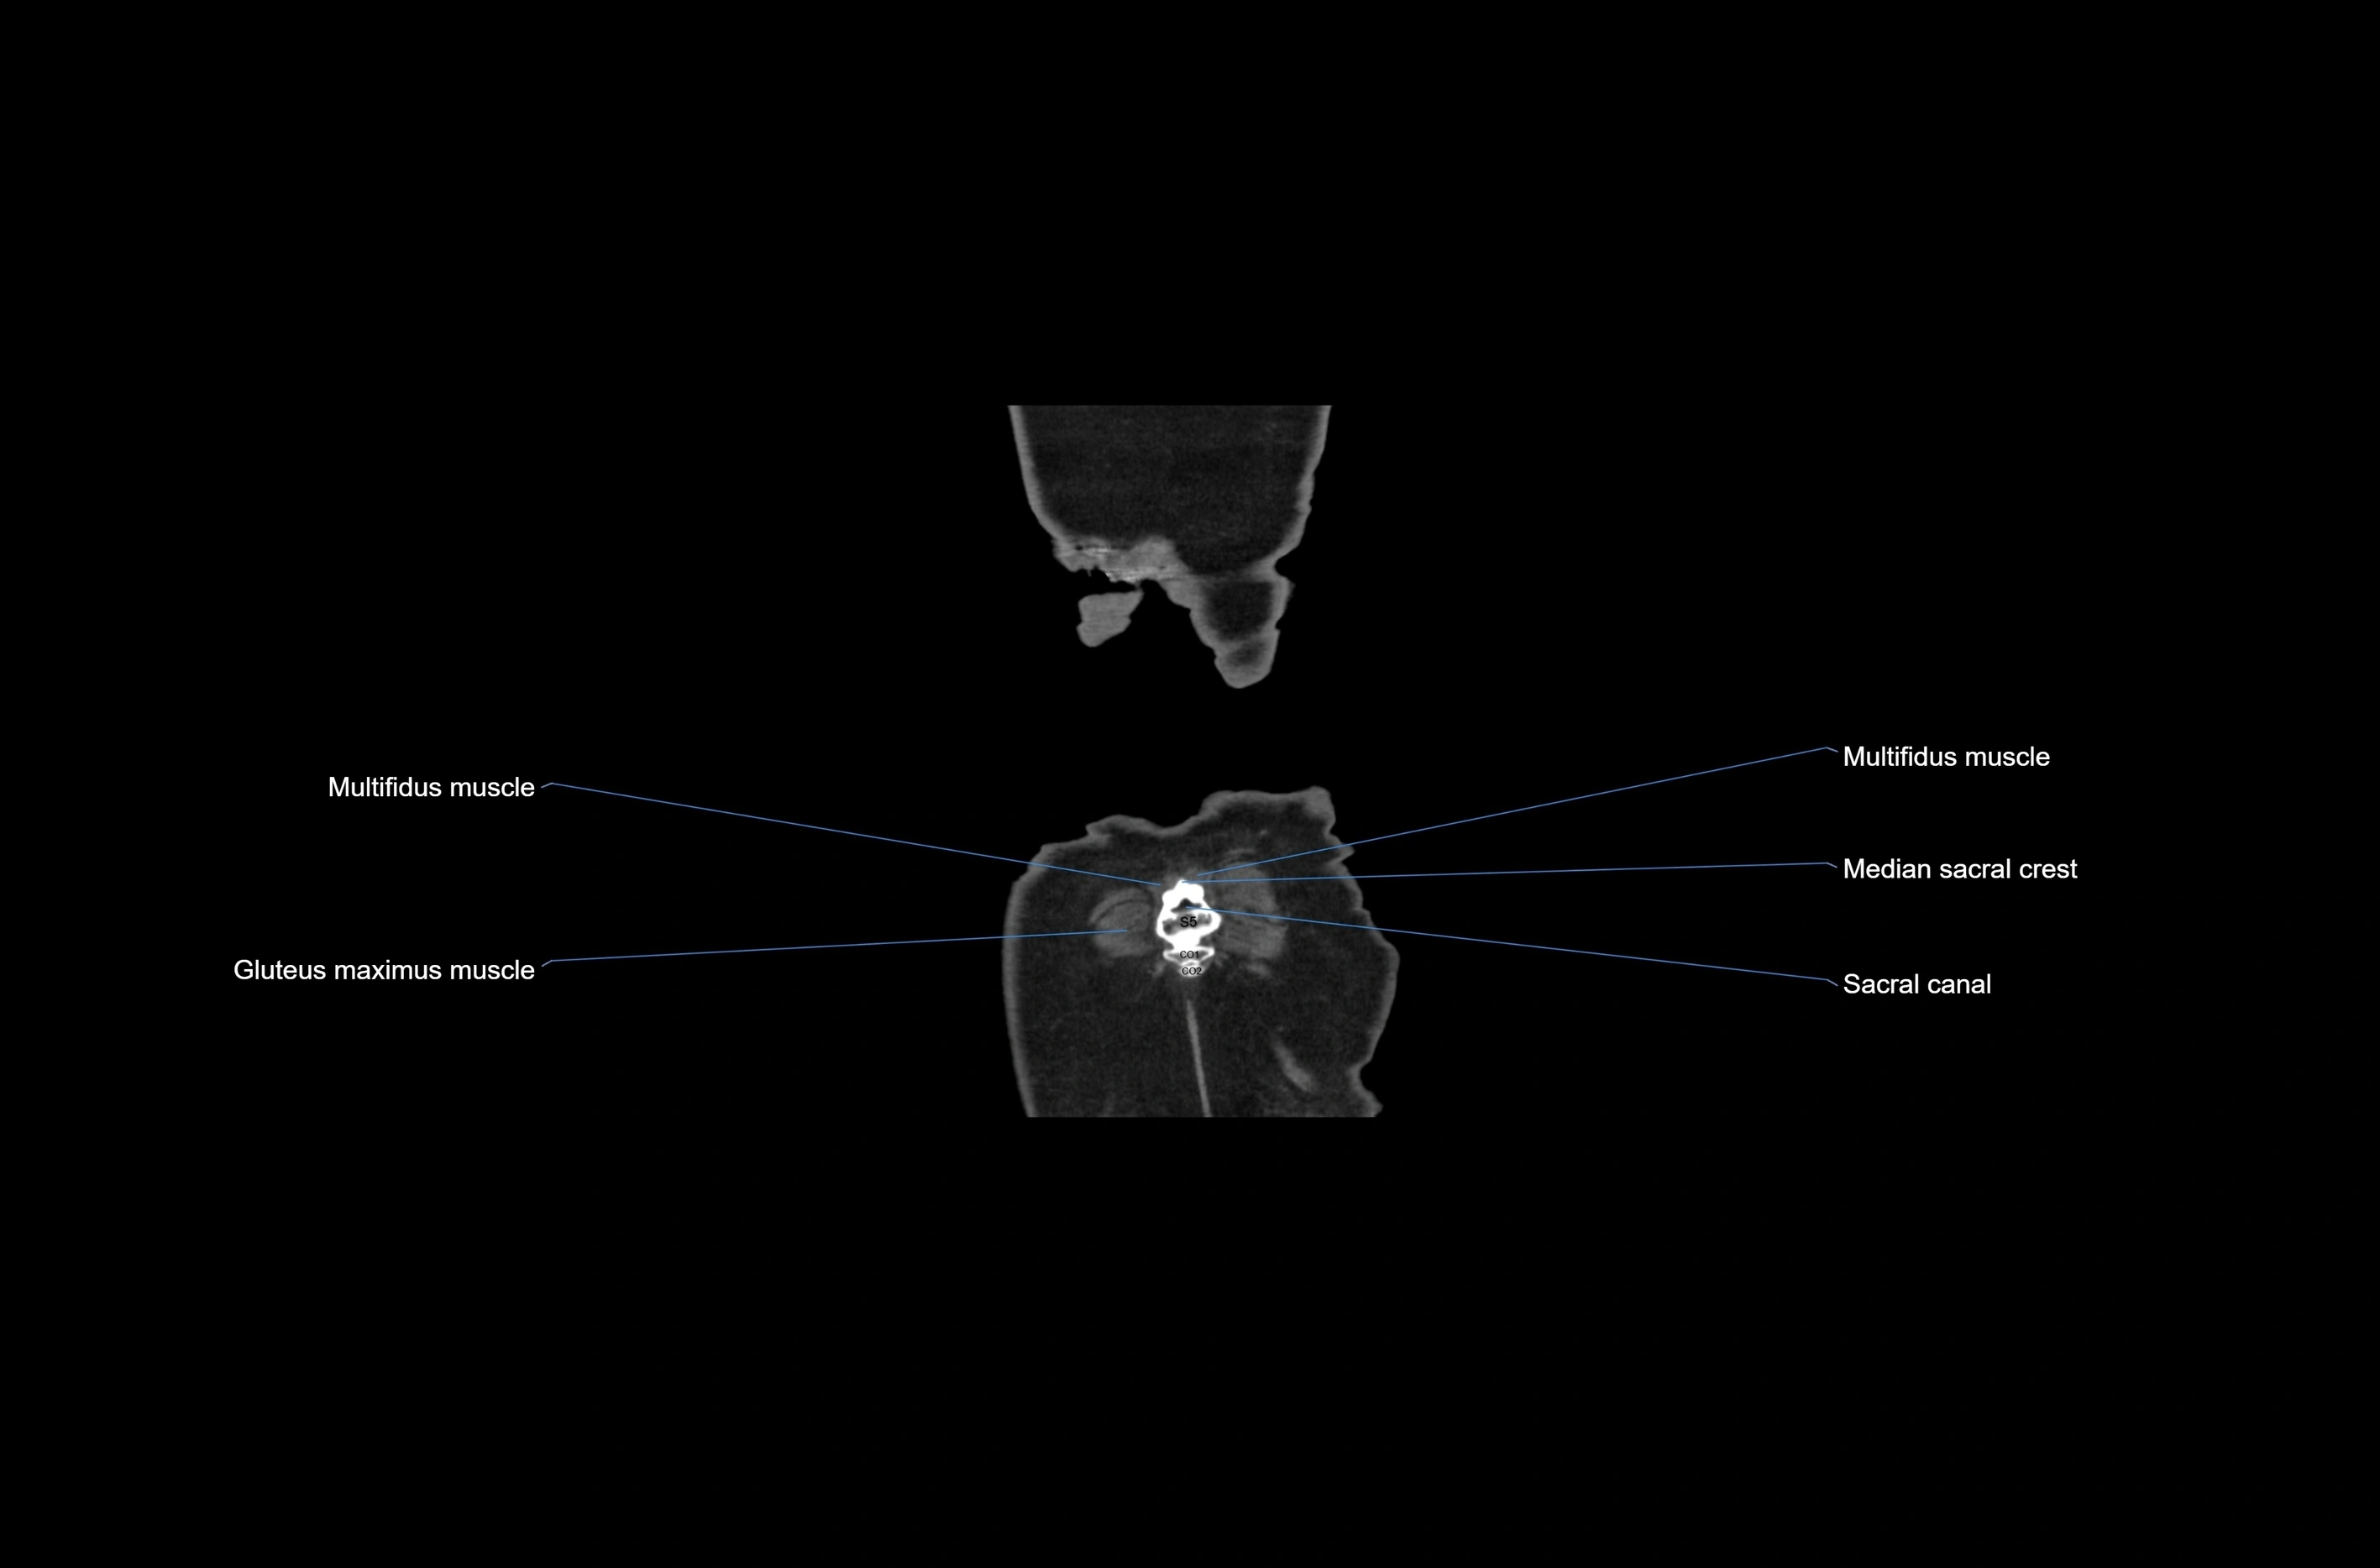

CT images